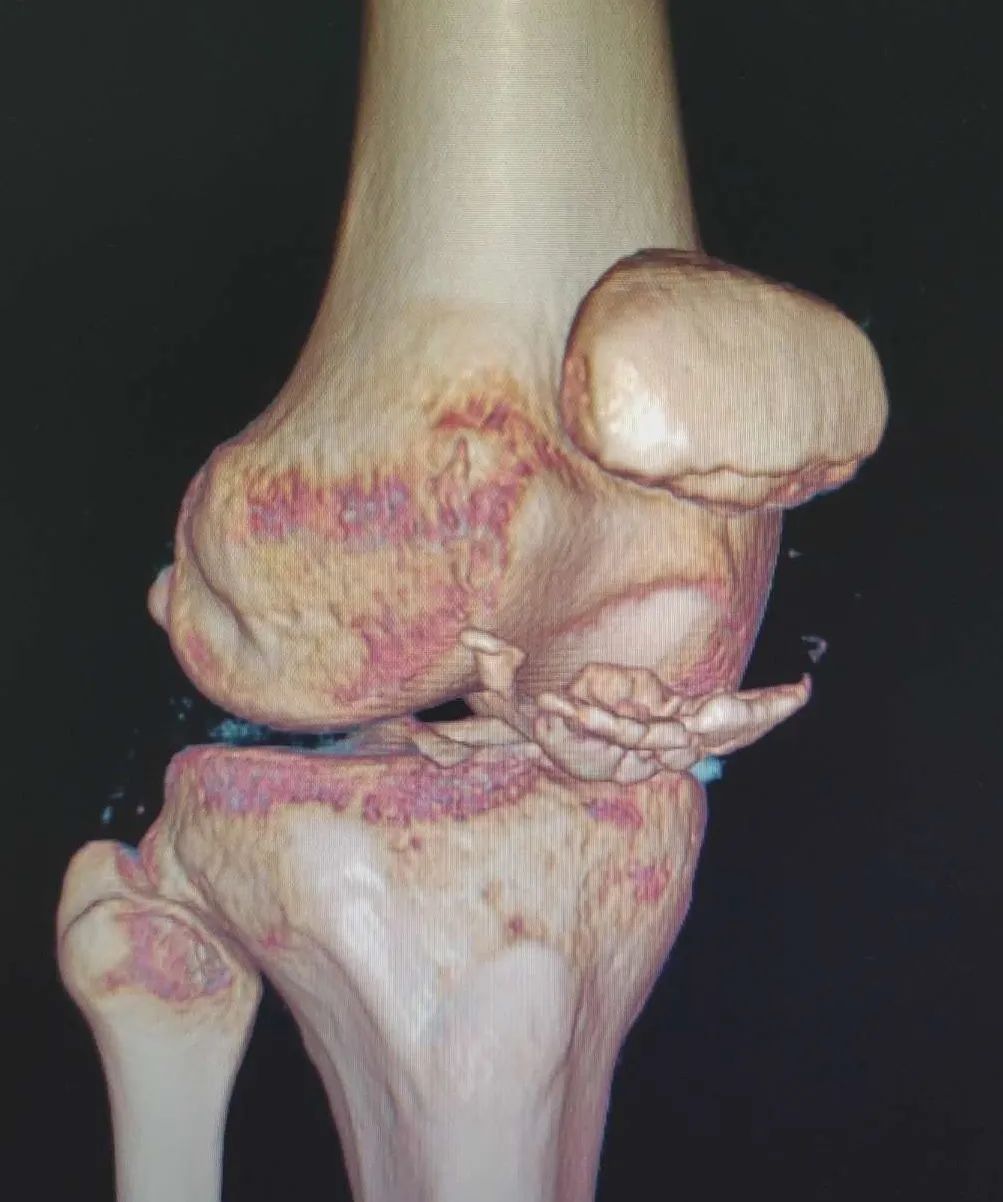

11月14日晚上,家住七雄街道的17岁少年天赐(化名)在骑电动车时不慎摔倒致右膝受伤,随即感到伤处持续性剧烈锐痛,遂来我院就诊。接诊医生经仔细查体并结合X线摄片,诊断天赐为“髌骨骨折”,收住小儿外科病区。入院后,积极完善各项相关检查,进一步CT检查提示:髌骨远端粉碎性骨折。

▲X线摄片显示:髌骨下级撕脱骨折

▲CT检查显示:髌骨远端粉碎性骨折